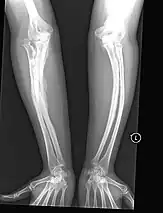

The main symptom of osteogenesis imperfecta is fragile, low mineral density bones; all types of OI have some bone involvement.[5] In moderate and especially severe OI, the long bones may be bowed, sometimes extremely so.[28] The weakness of the bones causes them to fracture easily; a study in Pakistan found an average of 5.8 fractures per year in untreated children.[29] Fractures typically occur much less after puberty, but begin to increase again in women after menopause and in men between the ages of 60 and 80.[1]: 486

Diagnosis is typically based on medical imaging, including plain X-rays, and symptoms. In severe OI, signs on medical imaging include abnormalities in all extremities and in the spine.[97] As X-rays are often insensitive to the comparatively smaller bone density loss associated with type I OI, DEXA scans may be needed.[5]: 1514

Bone fractures are treated in individuals with osteogenesis imperfecta in much the same way as they are treated in the general population—OI bone heals at the same rate as non-OI bone.[1]: 431 A greater emphasis is placed on using lightweight materials to immobilize the fracture, as in moderate or severe types of OI, using heavy casts, such as hip spica casts, can cause fractures at the bones at the boundaries of the cast, as well as generalized osteopenia.[1]: 431 The lightweight cast or splint is then replaced with a removable orthosis after a few weeks and once evidence of union is seen on X-ray.[1]: 431 In order to prevent a nonunion or malunion, all fractures should be immobilized, even if the fracture seems trivial (microfracture),[1]: 439 as people with OI are at greater risk of nonunion.[1]: 438